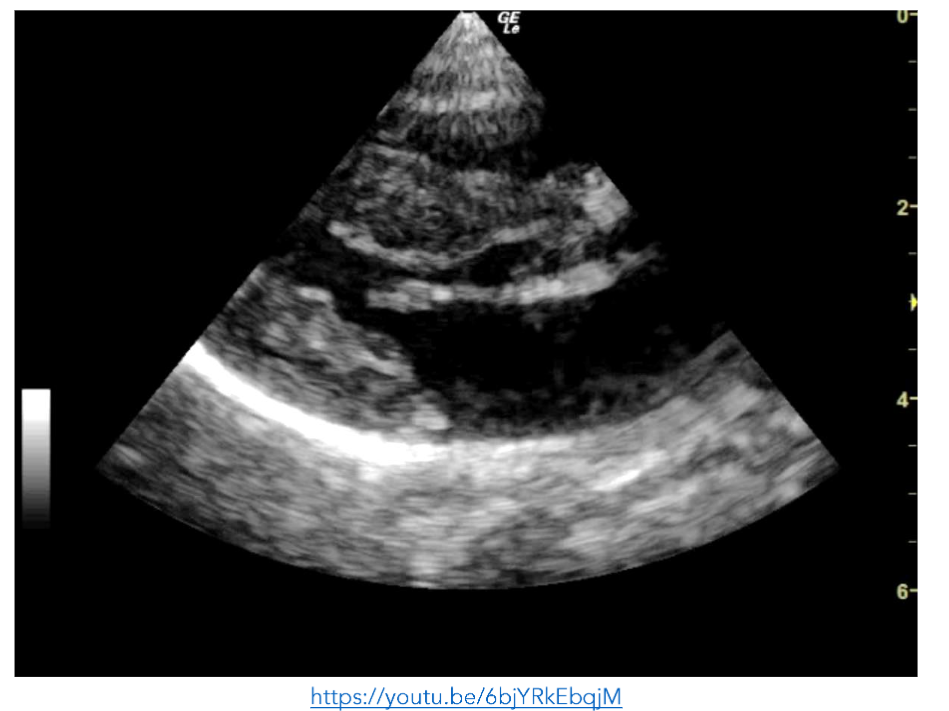

While in ED he developed a work of breathing and became hypoxic. Point of care echocardiography was repeated and showed a distended and plethoric IVC, with innumerable B-lines anteriorly.